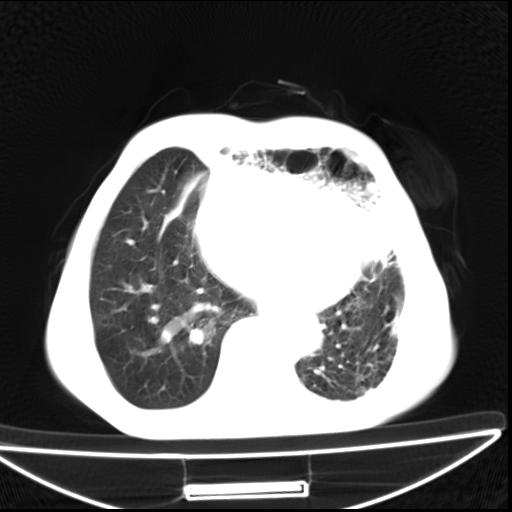

男  70岁,发烧咳嗽4天。盗汗,消瘦。无痰中带血丝,以前有肺tb病史,ct见,双肺tb,左侧胸廓塌陷,左胸膜肥厚粘连。纵隔移位,右侧胸腔积液,大家说说那个心影前左肺舌叶除了肺大炮还有炎症还是干酪性肺炎?有占位吗?我看纵隔淋巴结也大。

双肺继发性肺结核伴部分左肺毁损!

1)两肺继发性肺结核并左肺上叶肺不张,支气管扩张。2)双侧胸膜炎(胸膜增厚+少量胸腔积液)。